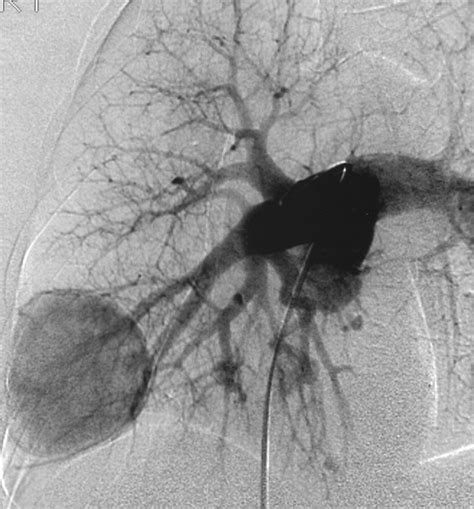

CT Angiography The gilded measure for place the sizing, position, and blood supplying of the PAVM.

Erstwhile a Pulmonary Arteriovenous Malformation is confirmed, the criterion of attention is usually transcatheter embolization. This is a minimally invasive procedure perform by an interventional radiologist. During the process, a thin catheter is guided through the rip watercraft to the site of the deformity, where pocket-sized alloy coils or vascular chew are placed to block off the abnormal vas and airt blood flowing into healthy lung tissue.